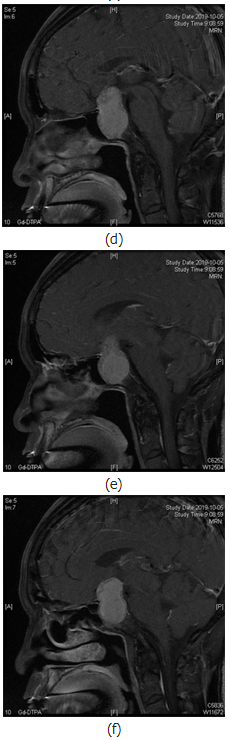

内分泌实验室检查未见明显异常,行颅脑CT示:蝶鞍扩大,鞍底下陷,鞍区及鞍上见团块状稍低密度影,边界欠清(见图1(a));鞍区MR动态增强示:蝶鞍扩大,鞍底下陷,鞍内及鞍上可见不规则短T1长T2信号,信号欠均匀(见图1(c)~(f));动态增强扫描边缘可见延迟强化,大小约41mm×38mm×25mm,边界清晰,视交叉受压上抬,移位,垂体柄显示不清,右侧海绵窦受累(图1(b)),考虑垂体瘤卒中。

图1.患者影像学检查资料。图1(a)示CT扫描下鞍区占位中存在低密度赢;图1(b)示鞍区平扫T2相鞍区占位内长短不一信号;图1(c)示增强磁共振扫描中鞍区占位内不均一信号;图1(a)~(c)均示垂体瘤内部有异常液体存在;图1(d)~(f)鞍区

但CT对急性期出血的确诊率高,且在显示骨质改变方面较MRI强。本例患者中可见患者颅内CT瘤体中存在明显的低密度影,而在MRI检查可发现患者T2相瘤体内部存在长信号影,考虑是患者瘤体内有出血,而患者增强MRI检查发现患者瘤体内部存在长短不一信号影,但是考虑患者肿瘤形态,患者卒中类型仅分类为不规则型,患者术中内镜观察肿瘤呈灰红色,切除过程中也发现血块,这一特点证实了患者垂体瘤卒中的诊断。